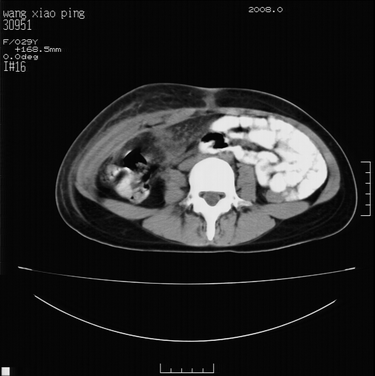

标题: CT13306:F,29,阑尾炎手术后20天,右下腹切口处包块. [打印本页]

标题: CT13306:F,29,阑尾炎手术后20天,右下腹切口处包块.

b超切口疝。

皮肤切口愈合良好。炎性肿块?

肿块密度较低,周围见有条索状影,边界不清,考虑为炎性病变可能大,必要是做增强看看。

支持阑尾术后切口感染。

切口处见液性密度影,周围肌肉肿胀,脂肪层密度增高。

符合术后并发症。